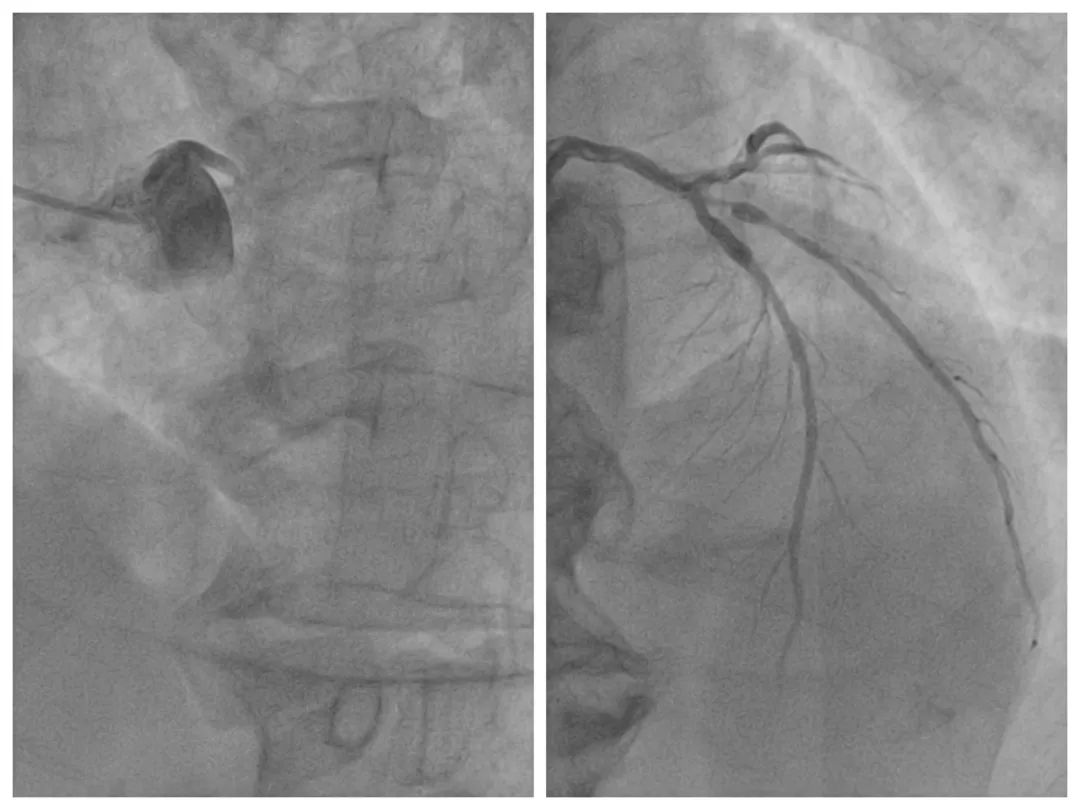

如此危重的病情,黄大爷正面临着生命危险,时间就是生命,时间就是心肌,来不得半点犹豫,我院胸痛中心陈丽媛主任医师、仇昌智副主任医师团队立即为患者开通救治绿色通道,第一时间将患者送到介入室,为患者紧急开通闭塞的血管。在左主干-前降支开口(LM-LAD)植入一枚药物支架,同时植入主动脉球囊反搏(IABP)加强循环支持治疗,整个救治过程流畅快速。手术过程顺利,仅48分钟的时间,闭塞血管便得以开通,术后,将患者送到重症监护室进一步密切监护。

▲术前(左图)左主干中段后完全闭塞,术后闭塞血管得以开通(右图)